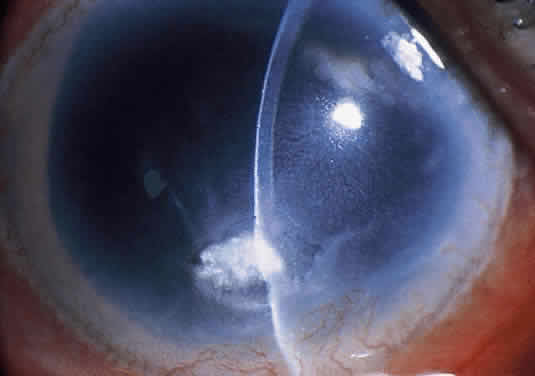

Clinically, a bacterial corneal ulcer caused by Pseudomonas aeruginosa evolves quite rapidly and involves large areas of the cornea. It is frequently seen in a debilitated, elderly patient, and especially in those wearing extended-wear aphakic contact lenses.11,15 It generally begins centrally with a gray infiltrate that has an overlying epithelial defect. The adjacent cornea often has a hazy appearance secondary to epithelial and stromal edema. The ulcer commonly has a yellow green discharge and a “soupy” appearance (Fig. 9). The discharge contains both fluorescein and pyocyanin pigments and fluoresces with Wood's lamp (but not with the cobalt blue light of the slit lamp biomicroscope).71

Fig. 9. Rapidly progressive Pseudomonas aeruginosa corneal ulcer in a 65-year-old man. Note the characteristic soupy appearance of the infiltrate and the mucopurulent discharge adherent to the ulcer bed.

Ring abscesses can occur and may represent antigen-antibody reactions to exotoxin or other substances.72 A large, sterile hypopyon is frequently present and should not be mistaken for endophthalmitis. The infection spreads rapidly in all directions without treatment and can involve the sclera, with serious consequences, or can cause corneal destruction with perforation.73 Occasionally, the clinical course is much more indolent.71 In patients with HIV infection, the keratitis may be much more resistant to therapy.74